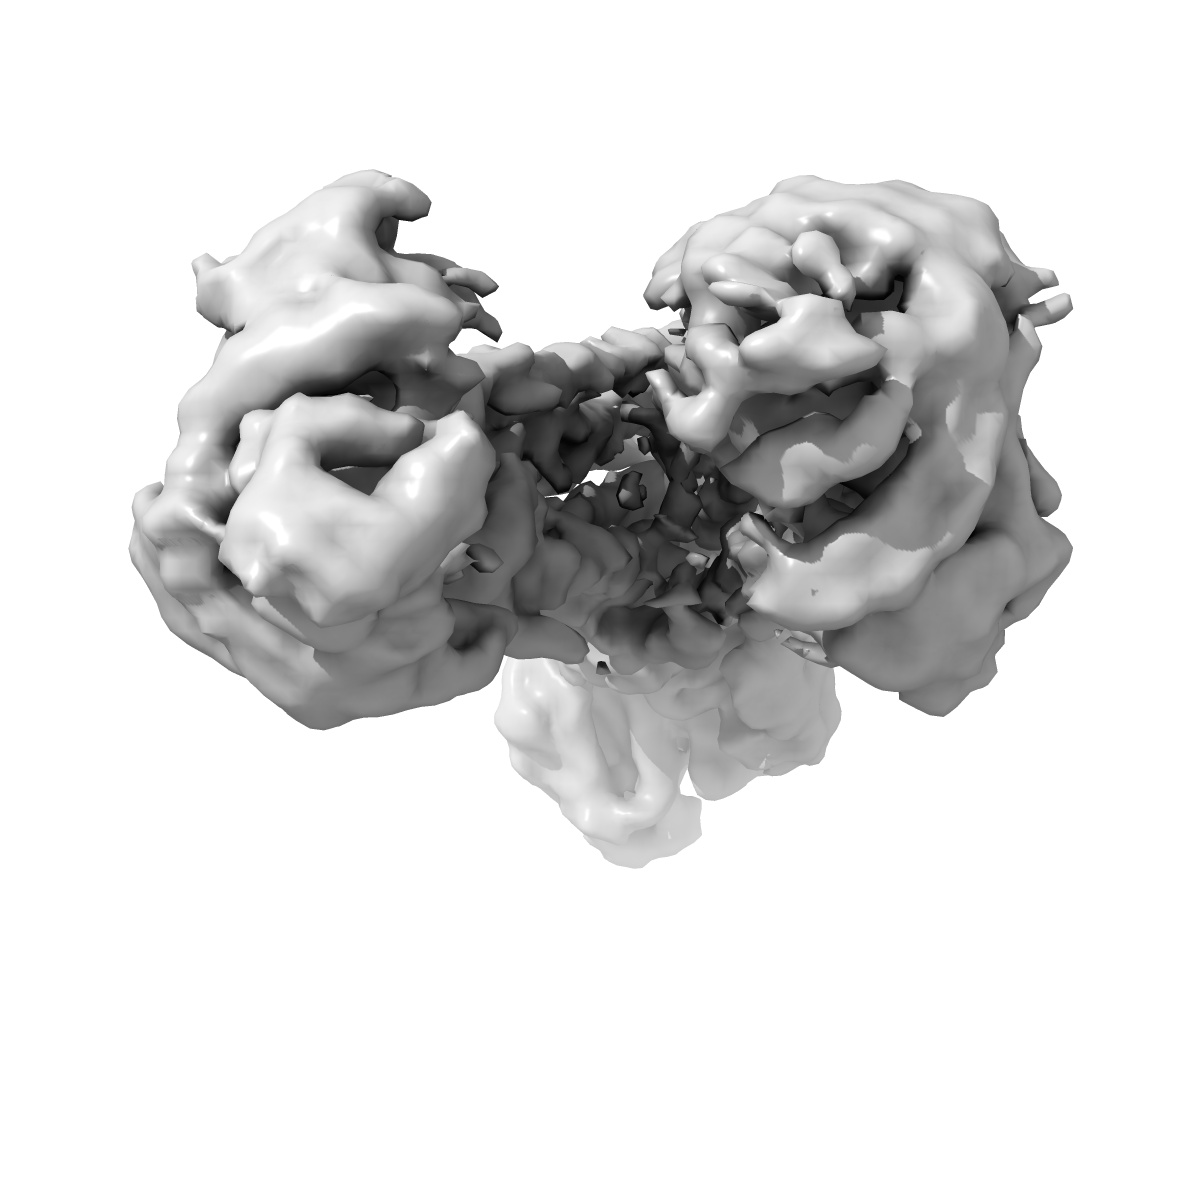

Amphipol reconstituted UIC2 Fab complex of double EQ mutant of human-mouse chimeric ABCB1 (ABCB1HMEQ)

Sample: Amphipol reconstituted UIC2 Fab complex of double EQ mutant of human-mouse chimeric ABCB1 (ABCB1HMEQ)

Structure of a zosuquidar and UIC2-bound human-mouse chimeric ABCB1.

Alam A , Kung R, Kowal J , McLeod RA, Tremp N, Broude EV , Roninson IB, Stahlberg H , Locher KP

(2018) PNAS , 115 , E1973 - E1982